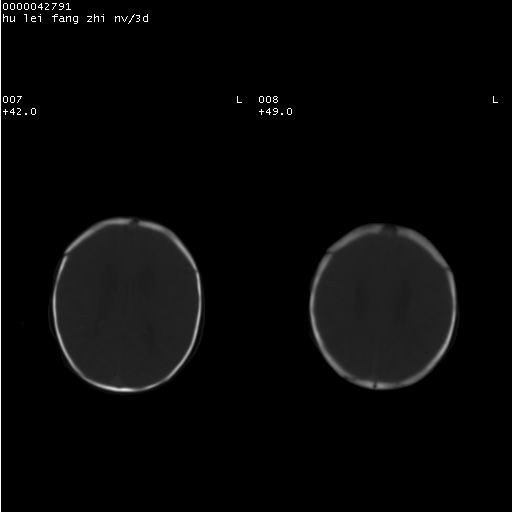

患儿 女,3天。惊跳,纳差。第二胎顺产,羊水ⅱ度。

临床诊断:hie?

颅脑ct轴位平扫(层厚、层距均为7mm),图像如下: